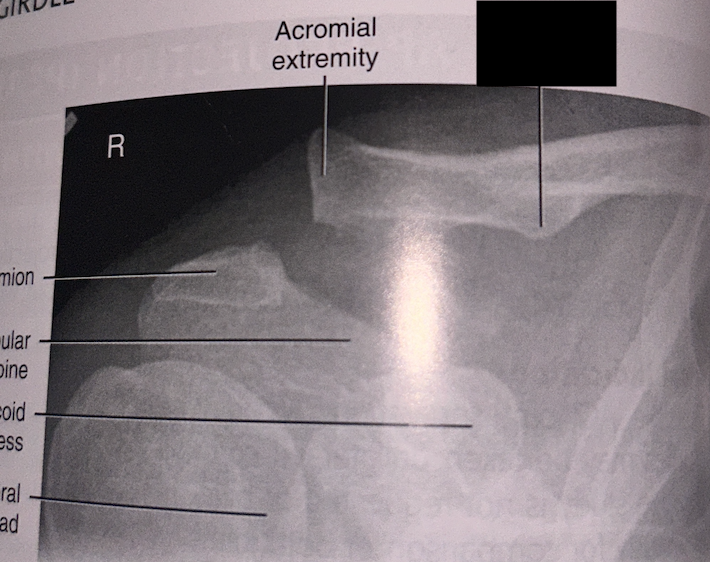

1

1st rib

2

clavicle

3

sternoclavicular joint

4

medial border scapula

5

inferior angle scapula

6

superior angle scapula

7

superior border scapula

8

coracoid process

9

glenoid fossa

10

lateral border scapula

12

acromioclavicular joint

13

acromion process

14

head of humerus

15

anatomical neck

16

greater tubercle

17

intertubercular groove

18

lesser tubercle

19

surgical neck